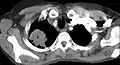

- Scanner thoracique